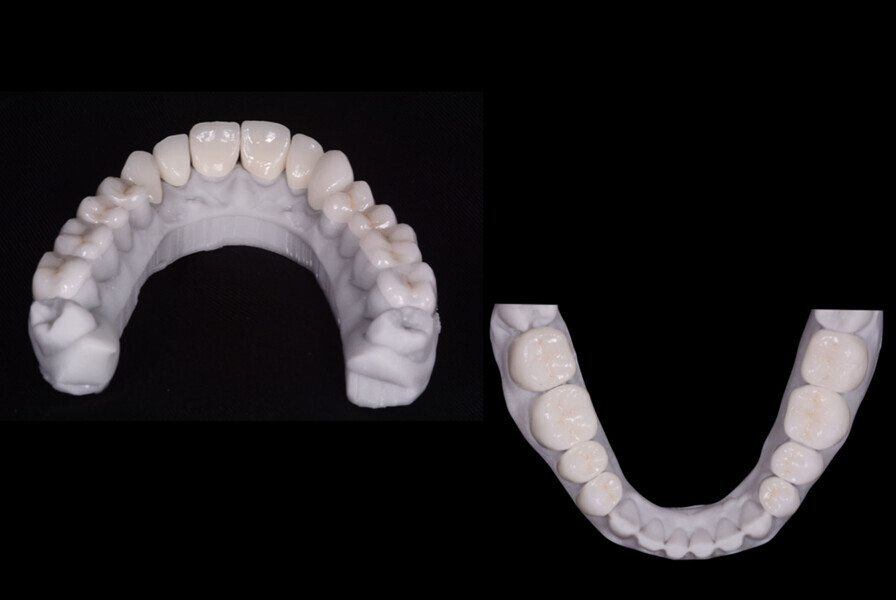

Fig. 11: The crowns (#11–13 and 21–23) and veneers (#14–17, 24–27, 31–37 and 41–47) were secured to the abutments using a light-cured resin adhesive (Futurabond U and Bifix QM).

Fig. 12: The crowns (#11–13 and 21–23) and veneers (#14–17, 24–27, 31–37 and 41–47) were secured to the abutments using a light-cured resin adhesive (Futurabond U and Bifix QM).